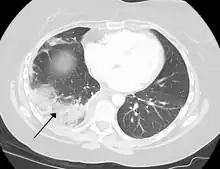

Infarction of the lung due to a pulmonary embolism

Because of the dual blood supply to the lungs from both the bronchial and the pulmonary circulation, this tissue is more resistant to infarction. An occlusion of the bronchial circulation does not cause infarction, but it can still occur in pulmonary embolism when the pulmonary circulation is blocked and the bronchial circulation cannot fully compensate for it.[2]